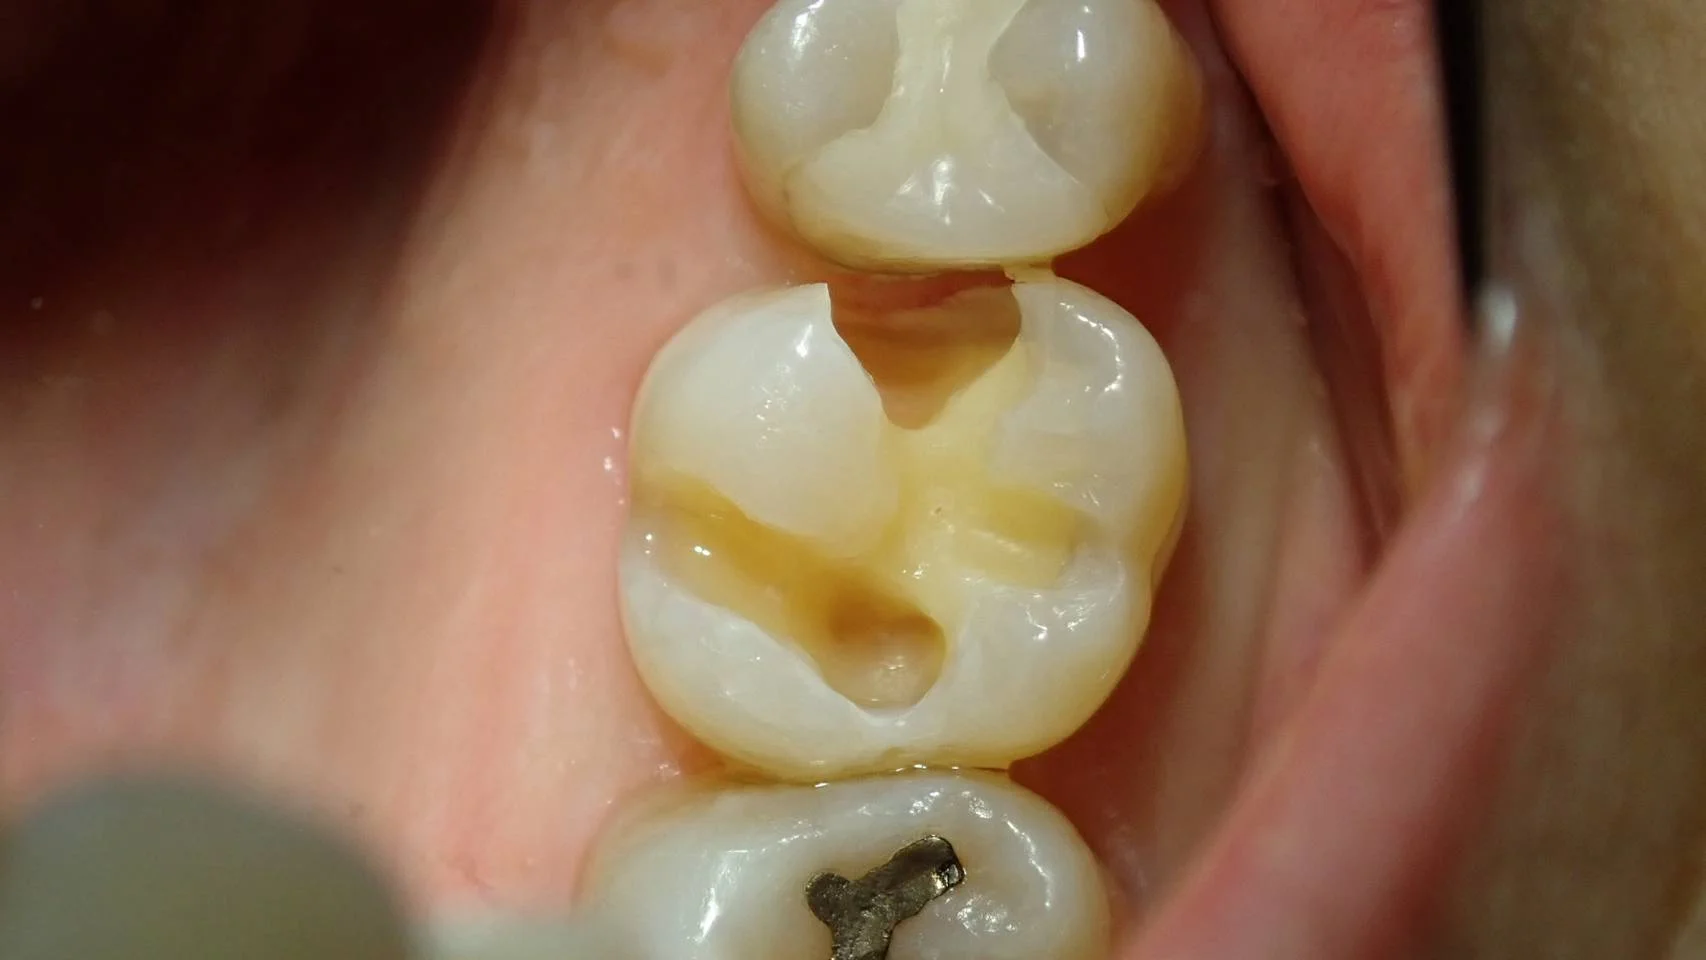

まずは、虫歯を取り切った充填前の写真です。

写真上だとあまり大きくないように感じるかもしれませんが、実際は上から見えないところで深くまで虫歯が入っており・・・ エナメル質という表層の固いところを残し、内面が大きくなくなってしまっている状況です。